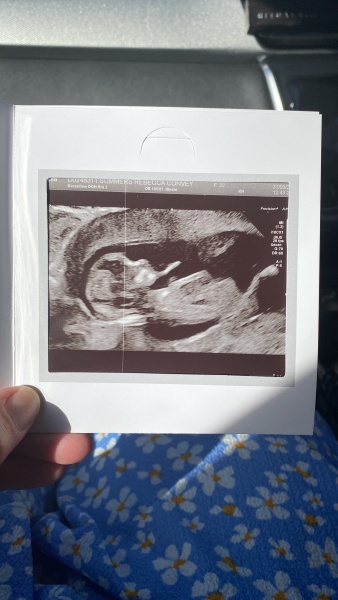

happy786 · 21/04/2026 19:20

help me guess please

Girl @happy786

thanks can you spot the nub

Boy